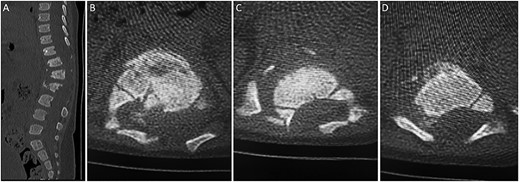

(A) sagittal thoracolumbar CT scan. (B–D) Axial thoracolumbar CT scan. (A-D) There are compression fractures and decreased vertebral body height of T12 and L1 with left pedicle and spinous process fractures. These fractures are associated with bony fragments within the spinal canal causing narrowing of the spinal canal at the same level. There is a nondisplaced fracture at the spinous process of L3 and the left transverse process of T10.